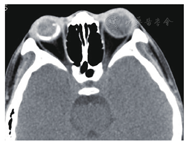

患者女性,8岁。因右眼视力下降1周于2009年1月22日就诊于遵义医学院眼科门诊。全身检查未见异常,自发病以来无眼部红肿、疼痛症状,无外伤史、中枢神经系统及全身疾病史。眼科检查:视力:右眼CF/40 cm,左眼0.8。裂隙灯显微镜检查眼前节未见明显异常。散瞳后眼底镜检查可见血管异常扩张,视网膜下方、黄斑区及颞侧见黄白色渗出,脂质沉着,病灶周围小血管扩张(图1)。荧光素眼底血管造影(FFA)显示右眼病灶内及周围视网膜毛细血管扩张,管壁荧光渗漏,微血管瘤,颞侧、颞下方网膜大片无灌注区,后期荧光增强(图2)。右眼OCT显示黄斑区网膜隆起,明显增厚,网膜下见不规则反射光带(图3)。诊断为右眼视网膜毛细血管扩张症。先后两次予右眼视网膜光凝治疗,治疗后7个月复查右眼视力为0.02。2012年患者因视力再次下降2月,到北京市第三人民医院就诊,B超显示右眼玻璃体混浊,下方及颞侧眼球壁钙化,其后可见声影,可见视网膜脱离(图4)。诊断为右眼视网膜毛细血管扩张症,未予特殊处理,建议观察。2014年患者再次到我院复诊,右眼视力CF/40 cm。右眼B超提示玻璃体混浊,可见眼球壁钙化(图5)。眼眶CT检查见右眼球轻度萎缩,右眼球两侧壁、后壁高密度影(图6)。诊断:右眼毛细血管扩张症晚期转化为眼球痨。

本例患者有典型的视网膜毛细血管扩张症的眼底表现,且眼底彩照及FFA也支持其诊断,CT及B超可见球后壁钙化,CT可见右眼球萎缩,因此我们考虑诊断为视网膜毛细血管扩张症晚期转化为眼球痨。孙为荣等[5]通过对诊断为视网膜毛细血管扩张症病理结果的观察发现视网膜毛细血管扩张症晚期可出现钙化及骨化。其主要原因可能为:(1视网膜毛细血管扩张症常见视网膜血管畸形扩张,这种血管畸形有时是以微血管瘤出现的,有血管瘤就会有钙化(本例患者初诊时FFA显示病变周围大量微血管瘤)。(2)视网膜毛细血管扩张症是一种缓慢反复的过程,可有新老病变交替,病情时重时轻,以后形成瘢痕组织成为增殖性视网膜炎,有瘢痕组织就有钙化的可能。病程长可能也增加了钙化的机会。本例病人初诊时视网膜下未见钙化,5年后随诊是眼底已窥不见,CT检查显示眼球两侧壁、后壁出现与眶骨一致的高密度影,提示合并钙化。毛细血管扩张症晚期转化为眼球痨需与脉络膜骨瘤相鉴别,后者常不伴其他眼部病变。目前该病例尚缺乏毛细血管扩张症晚期是否合并脉络膜钙化或脉络膜骨瘤的证据,毛细血管扩张症晚期是否会向脉络膜骨瘤转化,且二者之间是否存在某种关系,国内外均无资料报道,值得进一步探讨。